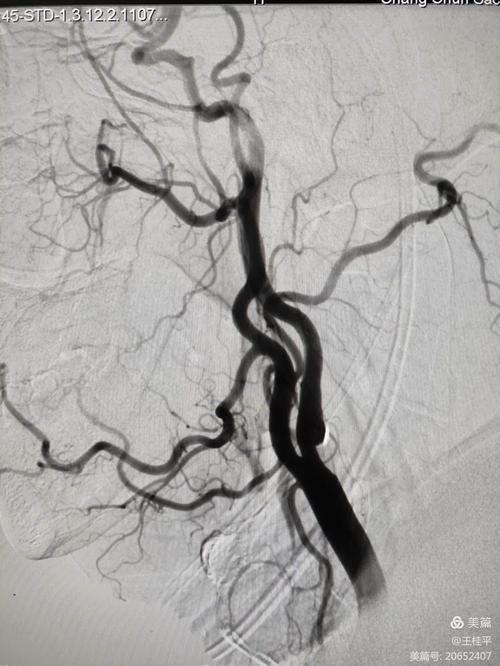

您提到的“右边血管”,最可能指的是右侧的颈动脉系统,我们的脑部供血主要来自两条颈动脉(左右各一)和两条椎动脉(左右各一),它们在颅内汇合成一个叫“Willis环”的结构,负责向整个大脑供血。

- 路径:脱落的血栓很容易进入右侧颈总动脉,然后上行到右侧颈内动脉,再进入大脑,由于左右大脑半球通过前交通动脉相连(Willis环的一部分),这个来自右侧的血栓可以“跨越”中线,堵塞左侧大脑中动脉或其分支,从而造成左侧脑梗。